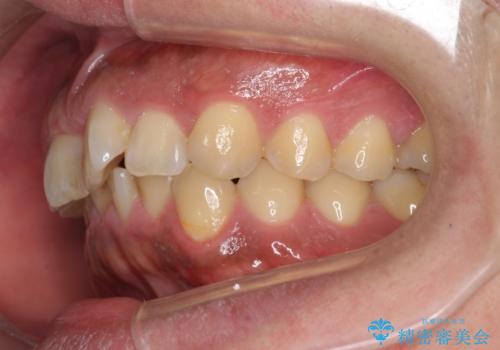

前歯のねじれを 1年かけずに矯正 インビザライン

- 前歯のねじれを主訴に来院。

インビザラインで治療しました。